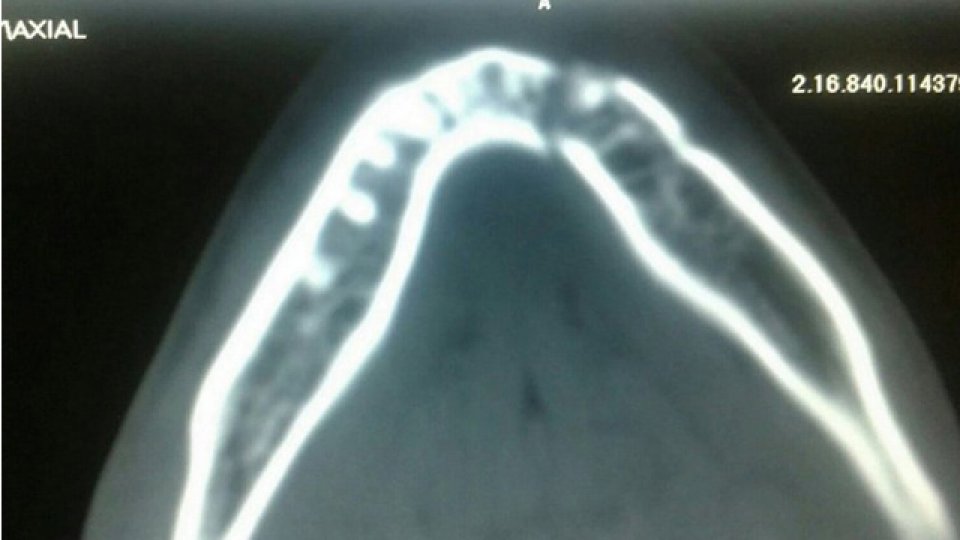

Imágenes de como quedó la mandíbula a Unsain por el golpe de Tevez.

Imágenes de como quedó la mandíbula a Unsain por el golpe de Tevez. Foto 1 de 2

El último sábado, en la Bombonera, Ezequiel Unsain vivió una de las peores pesadillas de su vida. Nada tuvo que ver el resultado adverso de Newell's ante Boca, sino que se debe a las consecuencias del rodillazo de Carlos Tevez, que le produjo la doble fractura del maxilar inferior. En su regreso a Rosario fue intervenido quirúrgicamente y ahora deberá mantenerse alejado de las canchas durante 45 días.

Después de eso, en las redes sociales se filtraron las imágenes de la radiografía de la mandíbula del joven de 20 años, que recibió el respaldo de la institución en el inicio de la recuperación y de diversos protagonistas del Mundo del Fútbol. Para el futbolista, lo peor todavía no fue superado: continúa sin hablar por el daño sufrido y solamente puede alimentarse con una dieta líquida, provista de papilla, flan y yogur.